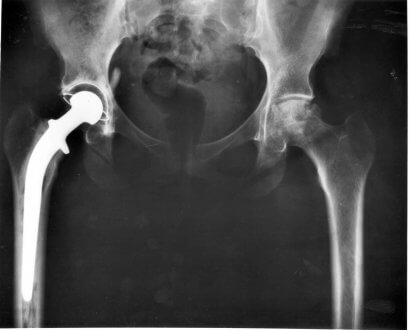

Selvom vi ikke kan rådgive om, hvor vidt det er en god idé at gennemgå operation, kan vi give dig de nødvendige oplysninger til selv at træffe beslutningen. For det første er det vigtigt at forstå, at ikke alle operationer virker. Der er imidlertid en relativt høj succesrate, når sygdommen diagnosticeres i tide.

Alt afhænger af hvad neurologen siger. Operationen kan undgås, hvis dyret stadig er i stand til at gå på trods af at have diskusprolaps, og hvis den professionelle siger, at diskussen kun stikker ud.

I så fald skal din hund gennemgå en seksugers behandlingsplan, der omfatter streng hvile, et supplement med kortikosteroider og en gastrisk beskytter.

Hvis du beslutter dig for at gennemføre operationen, bør du vide, at dyret skal have et par ugers total hvile. Chancerne for at kurere bagbensproblemer er høje.